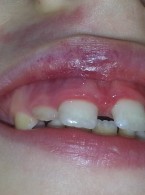

Do mojego gabinetu zgłosiła się 29-letnia kobieta ze zmianami erozyjnymi szkliwa. W wywiadzie pacjentka podała, że od dłuższego czasu przestrzega restrykcyjnej, niskokalorycznej diety i intensywnie uprawia sport. Czy lekarz dentysta może wysnuć podejrzenie anoreksji? Jakie objawy stomatologiczne mogą towarzyszyć temu schorzeniu?